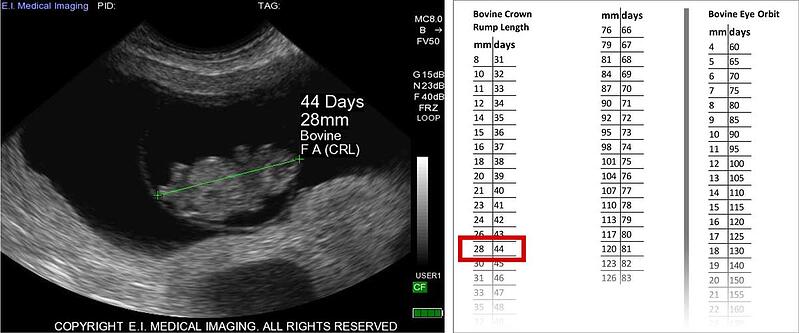

妊娠表— IBEX系统在其软件中内置了30多个妊娠表,可用于各种物种。将妊娠表应用于测量结果可用于对患者进行分期妊娠。这些数据表的参考资料可以在用户手册的后索引中找到。请注意,这些测量的准确性取决于每个表中数据点的数量,以及操作员准确冻结和测量结构的能力。